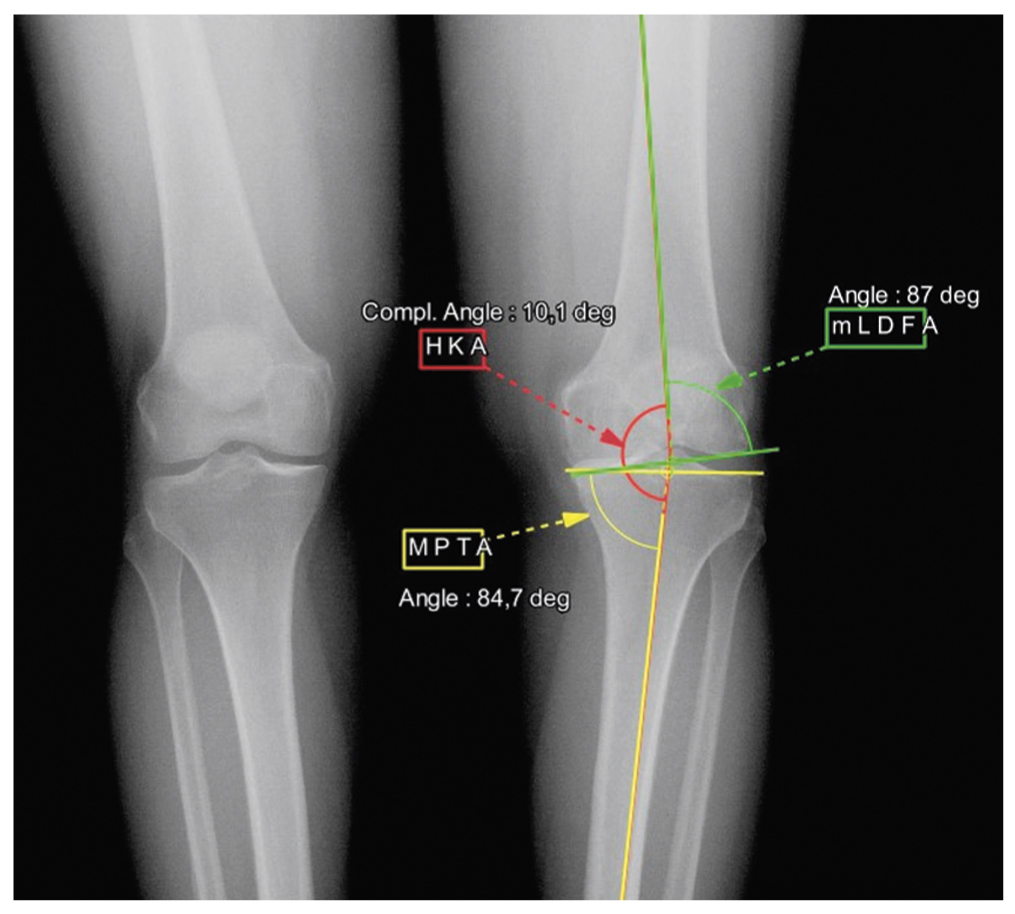

Через 6 мес после первичной остеотомии по данным топограммы в положении стоя у пациентки отмечалась выраженная вальгусная деформация нижней конечности до 11,2°, угол MPTA изменился с 84,7 до 97,9° (рис. 2).

Рис. 2. Топограмма нижних конечностей после первичной высокой тибиальной остеотомии. / Fig. 2. A topogram of the lower extremities after high tibial osteotomy.

При клиническом осмотре отмечалась вальгусная деформация: объем сгибания в коленном суставе составлял 110°, дефицит разгибания — 2°. Боль в коленном и голеностопном суставе по шкале ВАШ соответствовала 1 и 5 см соответственно; оценка по шкалам KOOS и AOFAS — 88 и 63 балла соответственно. Боль в голеностопном суставе левой ноги мы связывали с грубым нарушением биомеханики движений и механической нагрузки на голеностопный сустав. По данным топограмм до и после первичной операции, углы наклона суставной поверхности большеберцовой (tibial plafond inclination, TPI) и таранной (talar inclination, TI) кости значительно увеличились. TPI до операции был 3,4°, после операции — 11,6°, TI — 0,6° и 12,5° соответственно.